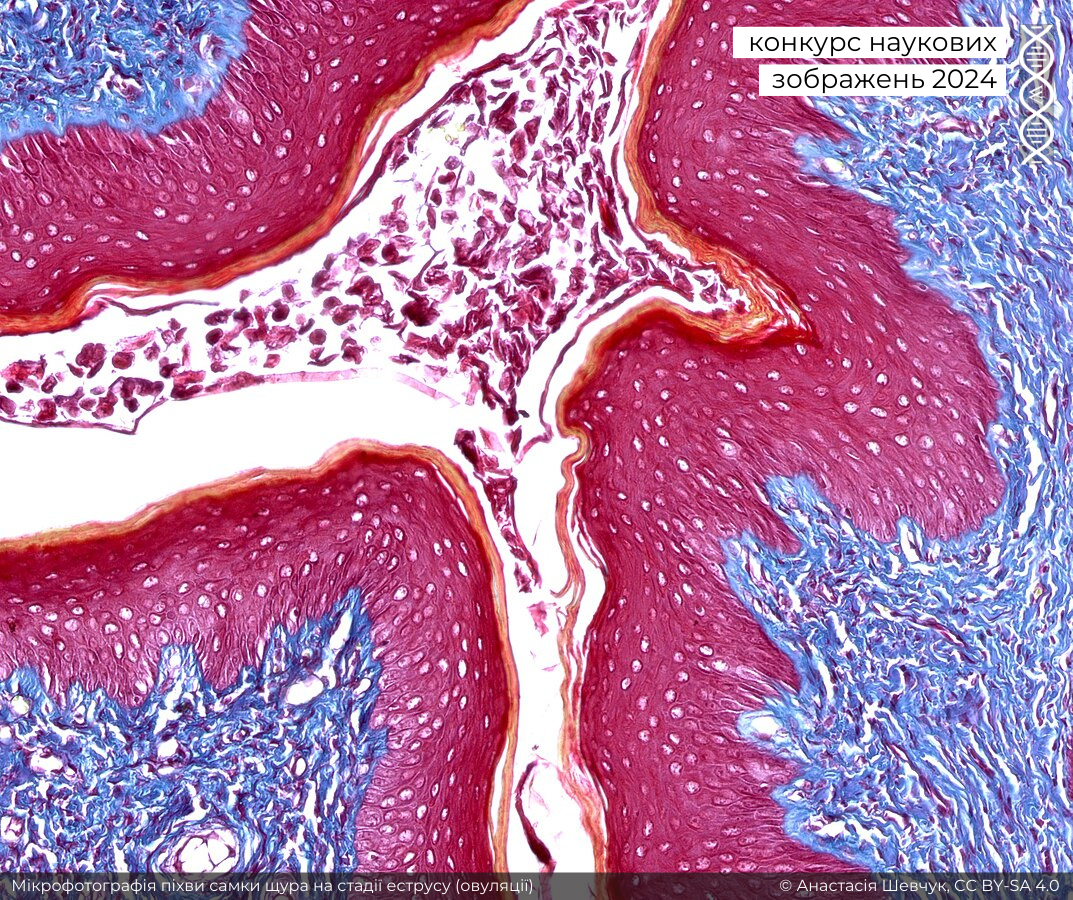

Однак моєю абсолютною фавориткою стала фотографія вагіни самиці щура в стадії еструсу, зроблена за допомогою трихромного фарбування за Массоном-Голднером. Цей знімок є унікально цінним для проєктів Вікімедіа, він має чудово написаний підпис, зрозумілий непрофесійному читачеві. Усі анатомічні структури на зображенні чіткі та різкі, чудово доповнені ідеальною експозицією та корекцією кольору.

Перше місце у номінації посіла мікрофотографія піхви самки щура на стадії еструсу (овуляції). Авторка — Анастасія Шевчук.

На цю стадію вказує зроговіння (жовто-оранжеве) багатошарового плоского незроговілого епітелію (червоний). Сполучна тканина забарвлена у синьо-зелений колір. Зрізи тканини зафарбовані трихромом Масона з використанням реагентів «Masson-Goldner Trichrome Staining Kit». Збільшення 260х. Мікрофотографія зроблена в Інституті експериментальної патології, онкології і радіобіології ім. Р.Є. Кавецького НАН України.Автори